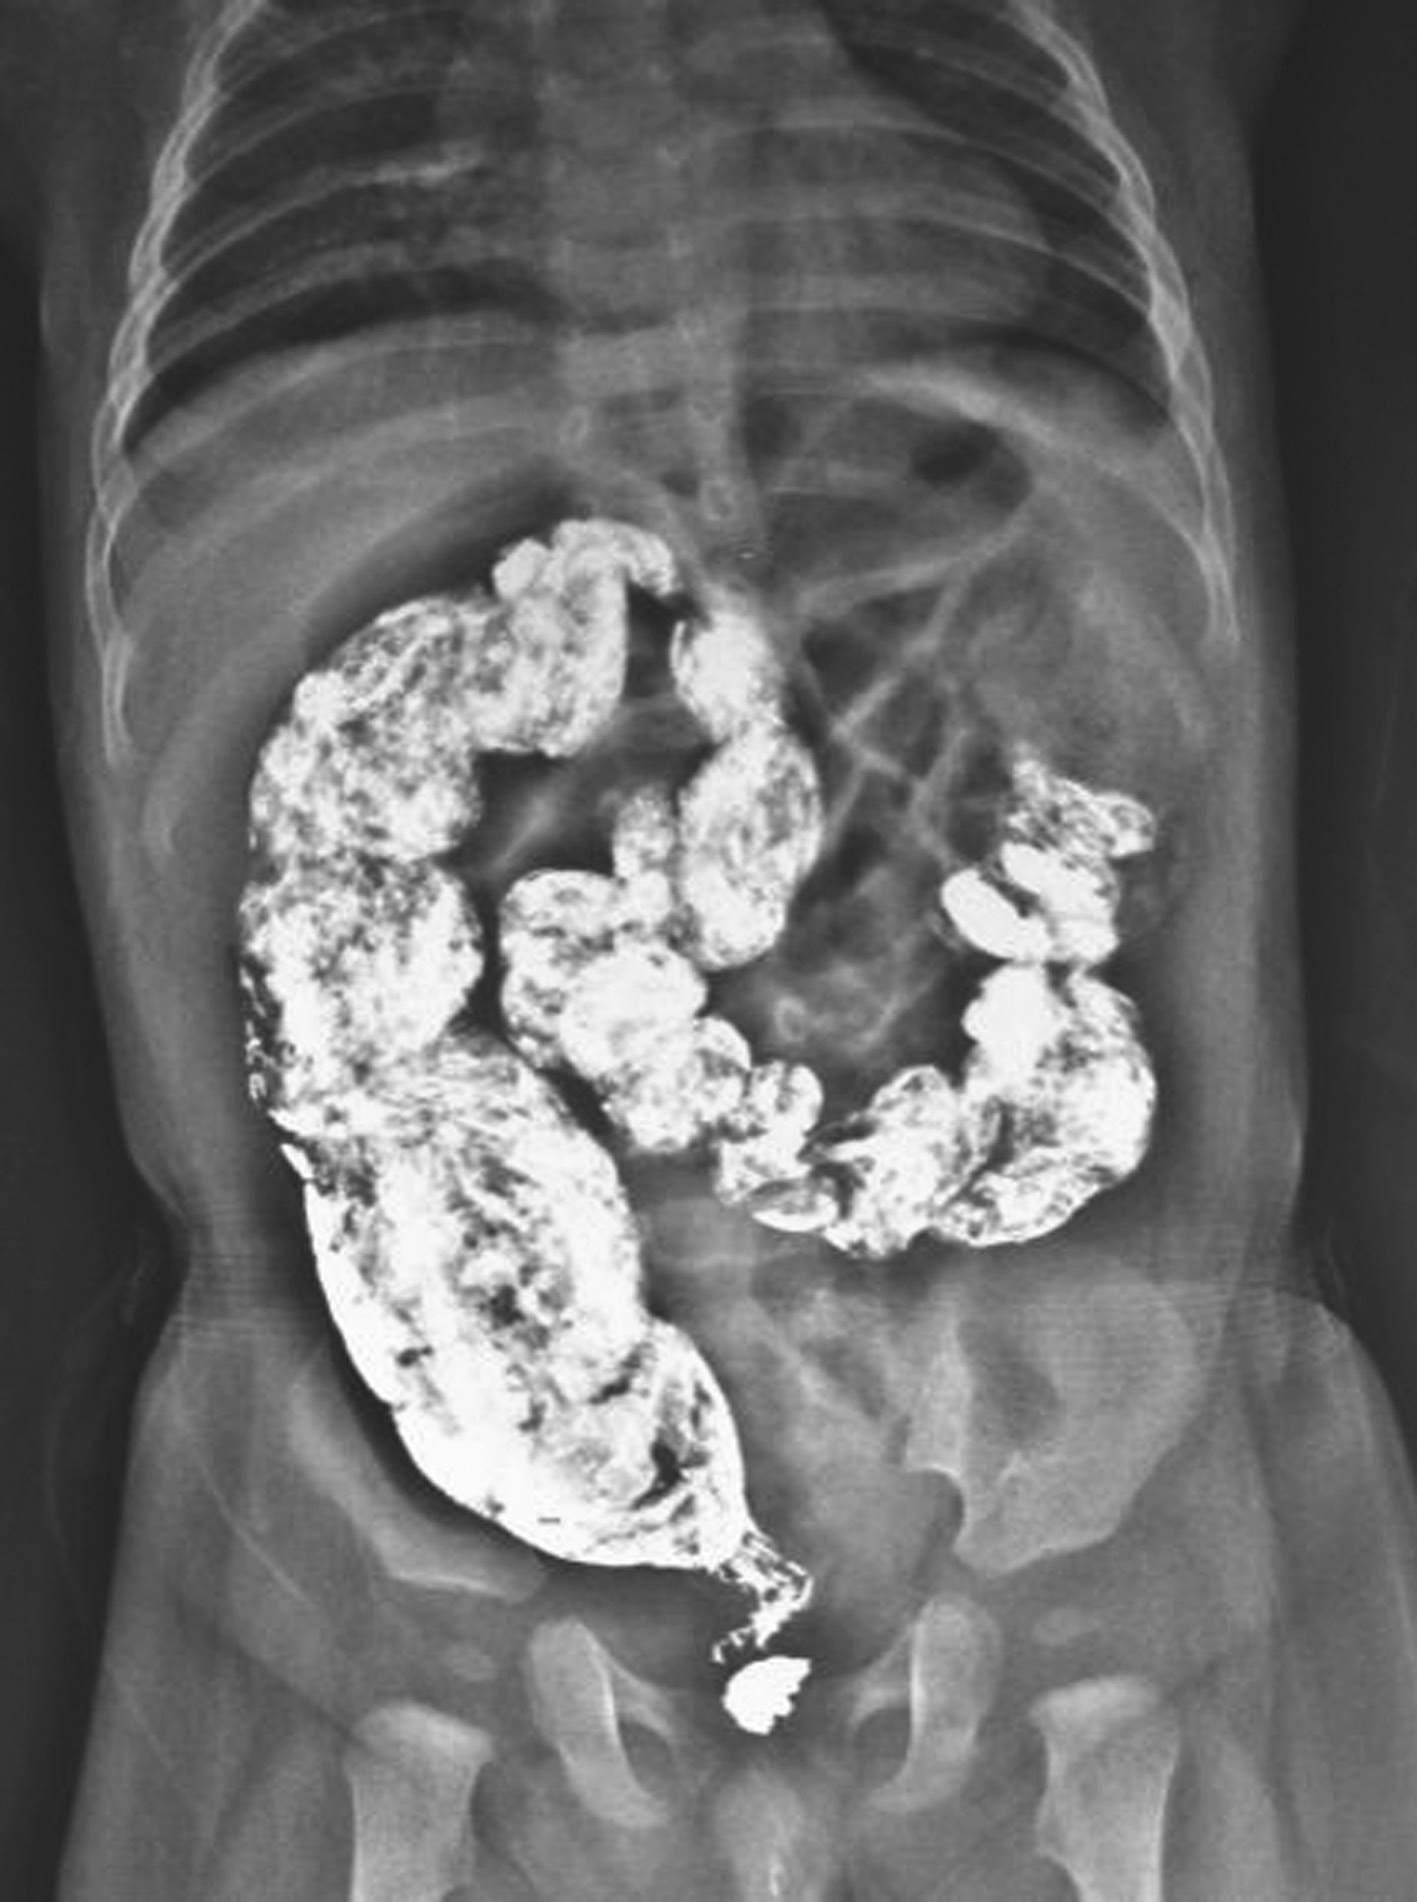

图3-18 钡剂灌肠

可见典型的狭窄段、扩张段及移行段。